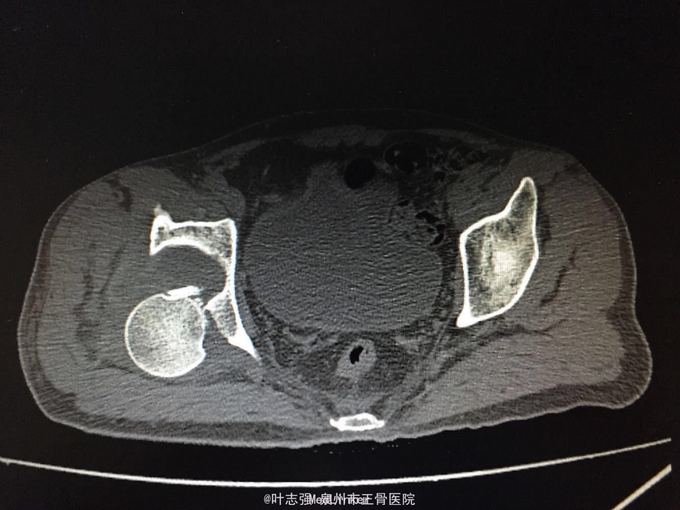

髋臼骨折伴髋关节后脱位ORIF

车祸致左髋部疼痛、活动受限1天。 53岁男性

左髋臼骨折伴髋关节后脱位 行生命支持,股骨髁上骨牵引,